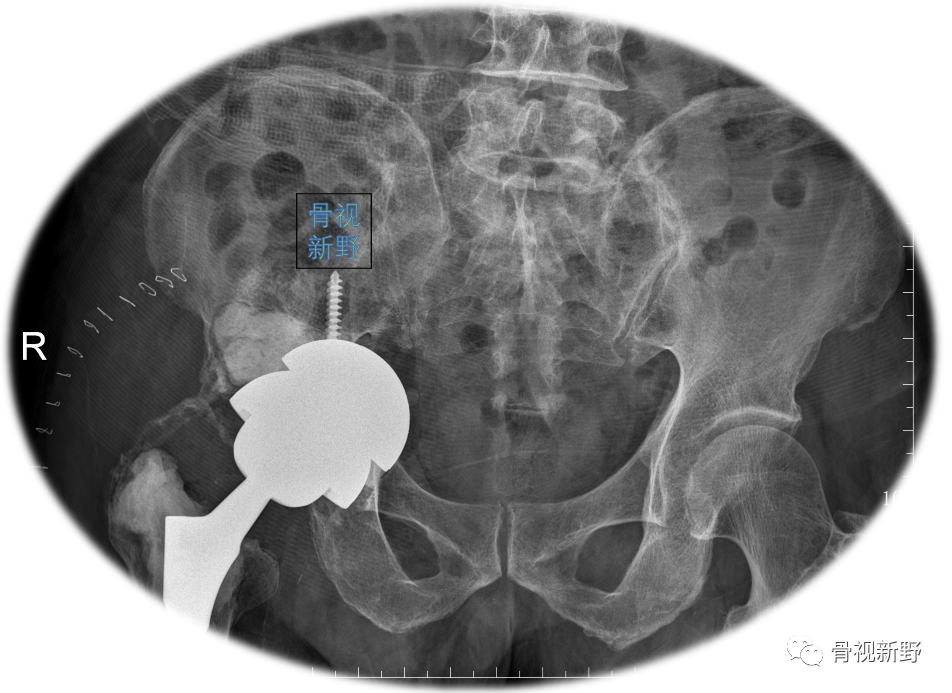

Case 1: Paprosky IIIb

男性,78岁。因右髋部骨折,于25年前行右髋THA。入院前半年开始出现右髋部疼痛、活动受限,加重1月。影像资料提示假体松动、移位;股骨侧及髋臼侧严重骨缺损(Paprosky IIIb )。

完善术前常规检查后,择期行翻修术:髋臼侧以cup-in-cup技术翻修;股骨侧以水泥柄翻修。

术后X光片